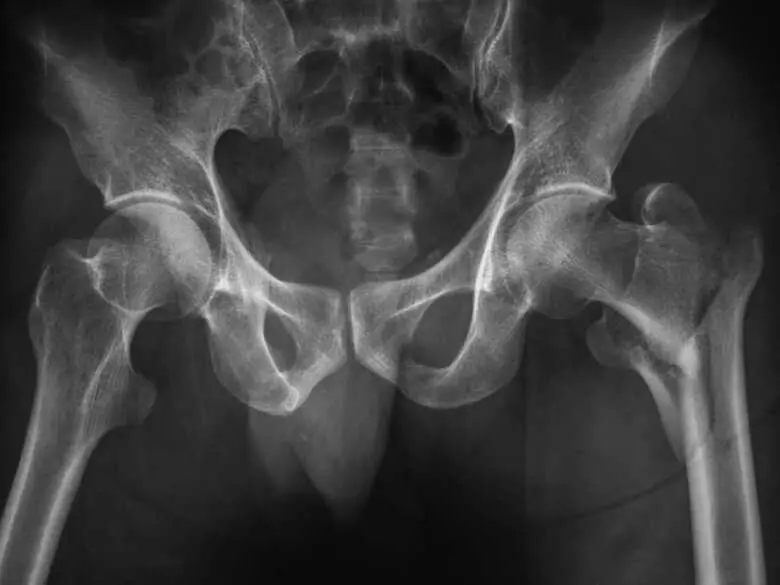

Zdjęcie RTG bioder